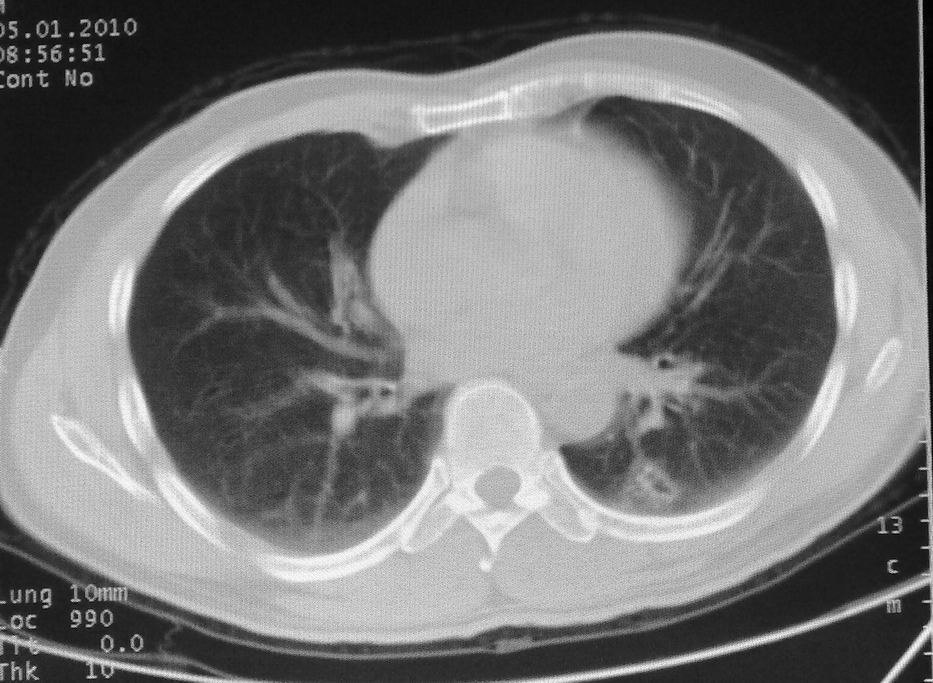

男,51岁,左胸前区不适数天。

薄壁空洞,边缘毛刺,胸膜凹陷,考虑肺癌,结核不排除。

考虑左肺下叶感染性病变。

考虑左肺下叶感染性病变,不除外肺栓。